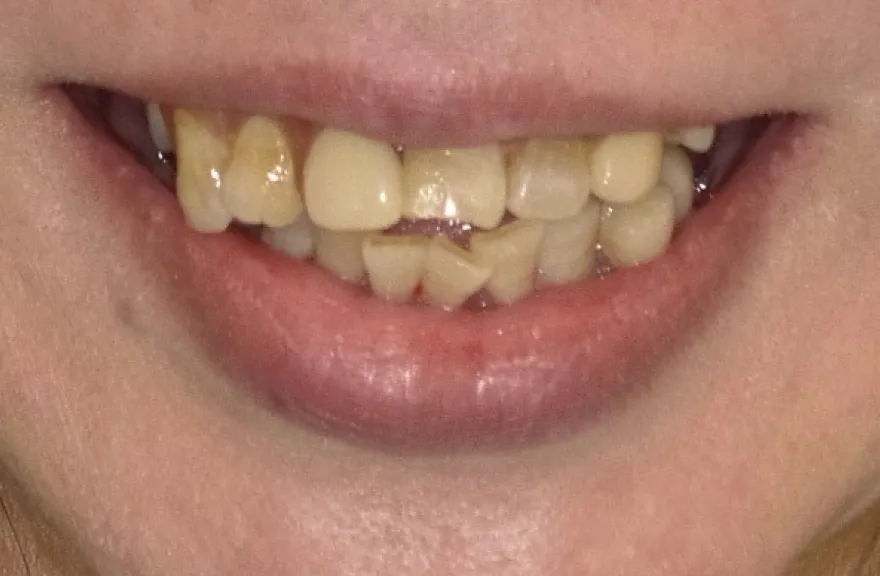

【治療例 3】奥歯が痛い、全体的にみて欲しい 60歳

- 相談内容

-

今まで何回歯を入れてもトラブルが起きるために、奥の歯を入れないまま今日に至る、ということでした。

噛み合わせ・骨格を読み解き、今後の人生でトラブルが起きにくいように全体的な治療計画を練りました。 - 治療費用・方針

骨格の前後的な差がある方でした。術前のレントゲンより、上下で歯牙の損傷に明らかな差があるのがみてとれます。

上の歯がないところにインプラント治療を行い、上顎は全てインプラントフィクスチャーによる固定性の歯を入れられることも費用的には可能な方でした。

しかし、治療において重要なのは今目の前の歯を見ることではなく、なぜ目の前の歯になったかを考え、未来へ活かすことです。

骨格的な前後差を考慮することなく歯をいれても、装着した人工物は決して長持ちしません。

今回の症例では、敢えて上顎は総義歯形態をとり、骨格的な前後の差を解消するよう工夫しました。

上顎の残っていた歯も、差し歯としては使えずとも、敢えて根だけ残すことによって組織を温存し、義歯の安定に寄与するよう設計しました。

ここまで全体的にしっかり治療しておけば、今後の人生においてトラブルになるようなことにはならないでしょう。 - 治療のリスク